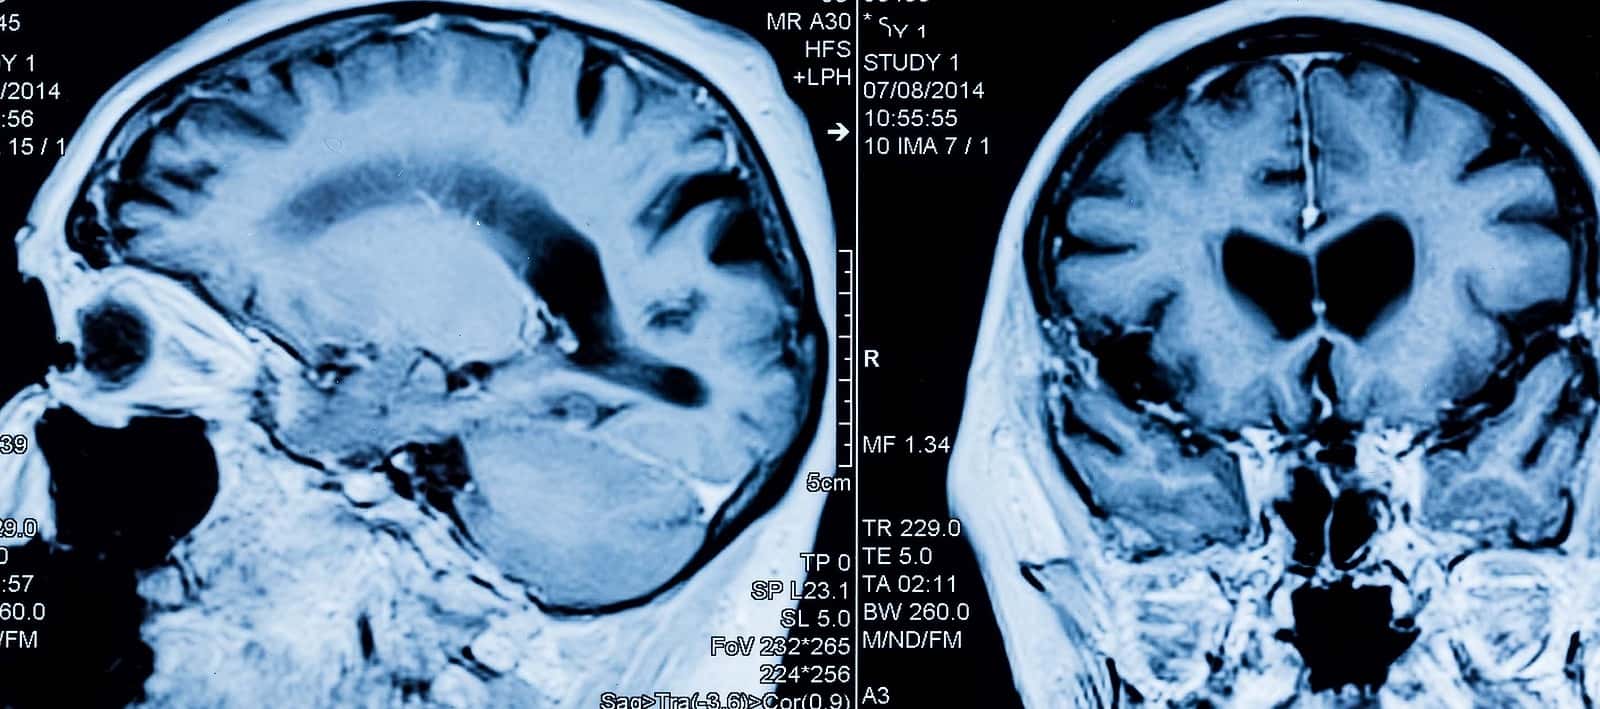

Most people are familiar with ultrasound being used as a diagnostic tool. They also know about using a magnifying glass to focus a ray of sunlight. With the proper technique, this could light a small fire. In focused ultrasound, the surgeon uses an acoustic lens to target ultrasound waves very precisely inside the body. Dr. Neal Kassell, our guest expert in this episode, is a neurosurgeon. He has used focused ultrasound primarily to treat brain tumors. Treatments require from several hundred to several thousand ultrasound waves.

Dr. Kassell described how ultrasound works for problems as dissimilar as liver tumors or essential tremor. There are multiple mechanisms, but scientists have concentrated on three: First, the beams of ultrasound generate heat that can destroy tissue where they are focused. So, tumor or tissue destruction is the first mode of action.